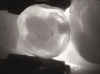

Fig 5. Case 1. NIR transillumination image of tooth No. 14 shows darkness on the mesial crossing the dentinoenamel junction.

Figure 5

Fig 8. Case 2. NIR transillumination image shows darkness around the composite and in the cracked region, indicating caries in both areas.

Figure 8